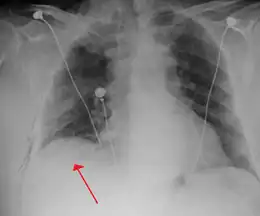

Anteroposterior inspired X-ray, showing subtle left-sided pneumothorax caused by port insertion

Lateral inspired X-ray at the same time, more clearly showing the pneumothorax posteriorly in this case

Anteroposterior expired X-ray at the same time, more clearly showing the pneumothorax in this case